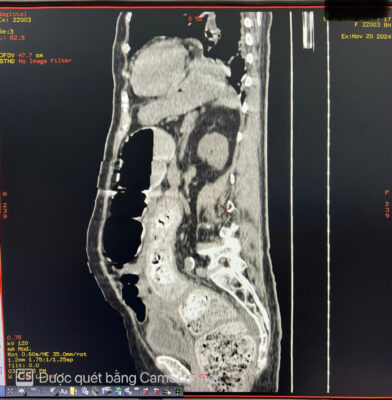

🚑 Một phụ nữ 84 tuổi đến khám với tình trạng đau bụng kèm táo bón mãn tính lâu ngày. Khi khám, bụng căng to, nhiều hơn ở bên trái. Sờ thấy một khối u mơ hồ ở hố chậu trái. Chụp X-quang bụng không chuẩn bị cho thấy giãn đại tràng lên và đại tràng ngang, toàn bộ đại tràng xuống chứa đầy phân. Các quai ruột non bị di lệch sang bên phải bụng. Siêu âm bụng thấy bụng căng nhiều hơi. Chụp cắt lớp vi tính (CT) ổ bụng cho thấy đại tràng xuống và đại tràng sigma giãn lớn chứa đầy phân kèm vôi hóa không đều tạo thành một khối u phân trong lòng đại tràng, có kích thước # 8 x9 x 26cm. Đại tràng lên và đại tràng ngang giãn d# 6.4 cm. Hai thận ứ nước độ I. Thành đại tràng dày nhẹ, còn cấu trúc lớp, thâm nhiễm mỡ nhẹ xung quanh, kèm ít dịch hạ vị. Không thấy khối u hoặc hẹp lòng ruột cản trở ở vùng trực tràng-sigma. Bệnh nhân được điều trị bảo tồn bằng thụt tháo và thuốc nhuận tràng. Hiện tại bệnh nhân ổn định, các triệu chứng cải thiện rõ rệt.

Hình ảnh 1 Hình ảnh 2

👉 Tóm lại: U phân là một dạng tắc nghẽn phân nghiêm trọng. U phân được hình thành do tình trạng ứ đọng phân trong đại tràng kéo dài, theo thời gian, các chất cặn bã này sẽ được sắp xếp lại để tạo thành một khối phân cứng, có hình dạng rõ ràng trong lòng đại tràng. Cũng có thể thấy vôi hóa. Đại tràng sigma và trực tràng là những vị trí thường gặp của u phân. U phân thường gặp ở bệnh Hirschsprung, bệnh Chagas, bệnh nhân nội trú bị chấn thương cột sống, bất thường về hành vi và ở bệnh nhân cao tuổi bị táo bón mãn tính. Các biến chứng của u phân bao gồm tắc ruột, loét đại tràng và thận ứ nước do ảnh hưởng của khối. Các lựa chọn điều trị bao gồm sử dụng thuốc thụt, thuốc nhuận tràng và làm sạch trực tràng để giảm tình trạng tắc nghẽn phân và can thiệp phẫu thuật nếu các phương pháp bảo tồn không hiệu quả.